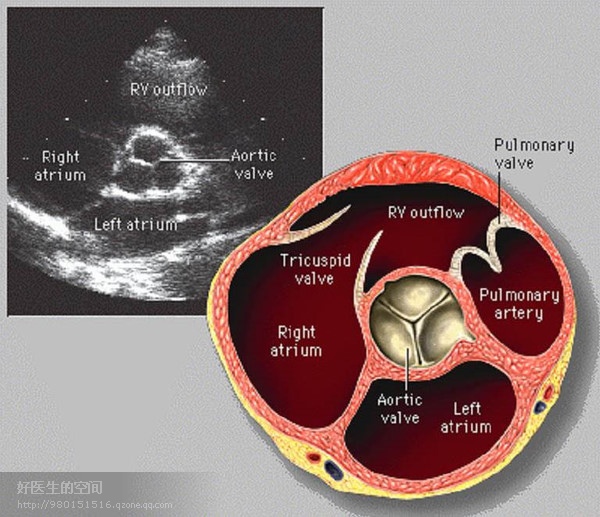

经典心脏超声切面图及解剖标示